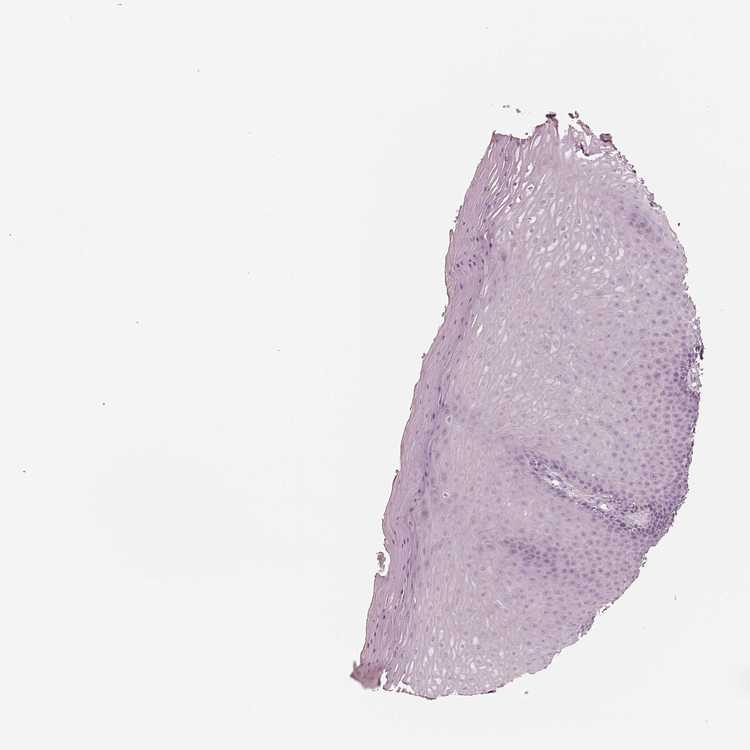

TISSUE PRIMARY DATA VAGINA Show tissue menu

VAGINA - Antibody stainingi

Antibody staining in the annotated cell types in the current human tissue is reported as not detected, low, medium, or high, based on conventional immunohistochemistry profiling in selected tissues. This score is based on the combination of the staining intensity and fraction of stained cells.

Each image is clickable and will lead to virtual microscopy that enables deeper exploration of all samples and also displays staining intensity scores, fraction scores and subcellular localization as well as patient and tissue information for each sample.

Antibody HPA070892

Squamous epithelial cells Not detected